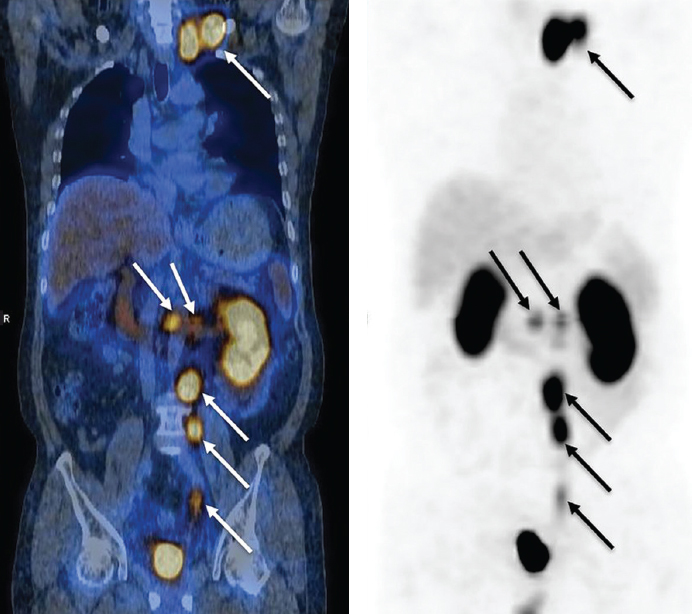

На рис. 7 приведены сцинтиграммы исследования РФЛП 68Ga-DOTATATE для диагностики и контроля эффективности терапии НЭО [25].

Рис. 7. НЭО – ВИПома, синдром Вернера-Моррисона, высокие дозы депо октреотида (Сандостатин ЛАР). После проведения одного цикла с 5 ГБк Y-90 DOTATATE не было показаний к назначению депо октреотида через 3 месяца, увеличение веса на 15 кг, значительное сокращение опухоли (частичная ремиссия). После 1 года наблюдения – нормальная функция печени и почек / Fig. 7. NET – VIPoma, Werner-Morrison syndrome, high doses of octreotide depot (Sandostatin LAR). After one cycle with 5 GBq Y-90 DOTATATE, there was no indication for octreotide depot at 3 months, weight gain of 15 kg, significant tumor reduction (partial remission). After 1 year of observation - normal liver and kidney function

На рис. 8 приведены сцинтиграммы исследования диагностической эффективности РФЛП с лигандом ПСМА, меченным 68Ga при РПЖ с целью планирования повторной терапии [26]

Рис. 8. Пациент с биохимическим рецидивом через 8,4 мес. после радикальной простатэктомии. 68Ga-ПСМА-617 на ПЭТ/КТ выявил метастаз в пресакральной и ретроперитонеальной зонах. Проведено облучения на выявленные пресакральные и подвздошные очаги (буст 66 Гр). После ИМРТ ПСА снизился до 0,02 нг/мл / Fig. 8. Patient with biochemical recurrence after 8.4 months. after radical prostatectomy. 68Ga-PSMA-617 on PET/CT revealed metastasis in the presacral and retroperitoneal zones. Irradiation was performed on the identified presacral and iliac lesions (boost 66 Gy). After IMRI, PSA dropped to 0.02 ng/ml

Представленный клинический случай показывает клиническую значимость проведения вторичной диагностики с РФЛП 68Ga-ПСМА для планирования последующей селективной терапии метастазов РПЖ.